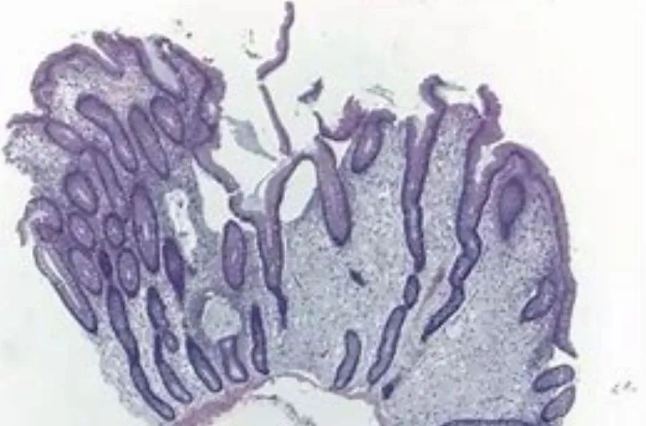

检查结果证实了大家的推测,患者胃镜提示:置底、体见弥漫性大小直径约0.5-2.0cm广基隆起,表面粗糙,边界清楚。胃窦见一大小约5x13cm隆起,呈分叶状.表面粘膜粗糙,边界尚清楚。肠镜见全结肠弥漫性大小约0.5-1.0cm 广基隆起。胃窦较大病变予取材送检,病检回报示:错构瘤性息肉。患者胃窦巨大病变,若不及时切除癌变风险极大,但患者年纪较轻,如果进行传统外科胃大部分切除术对患者后续生活质量影响较大。经讨论后,为患者进行胃镜下胃窦病变粘膜下剥离术为最佳手术方式,但是因患者病变巨大,手术难度大,剥离过程中出血及穿孔风险极大,这也为手术增加了不少难度。与此同时患者强烈要求就在本院进行手术治疗。

黑斑-息肉综合症 (Peutz-Jeghers syndrome, PJS) 是一种以胃肠道多发性息肉、皮肤黏膜色素沉着、患癌倾向为特征的常染色体显性遗传病。PJ 型错构瘤性息肉可出现在全消化道,其中以小肠最常见。胃肠道息肉可以导致慢性出血和贫血,还可以引起反复发作的肠梗阻和肠套叠,甚至癌变,患者需要多次外科手术治疗。黑斑-息肉综合征中的“黑斑”主要因为皮肤黏膜色素沉着,主要表现为自儿童期出现嘴、眼、鼻孔、肛周以及颊粘膜深蓝色至深褐色斑,手指色素沉着斑常见。大多黑斑在青春期和成年期可消退或变淡,但黏膜处比如嘴唇黑斑却很难消退。所以也有专家称其为“一眼望出来的病”。

黑斑息肉综合症患者发生多种恶性上皮肿瘤(结肠、 胃、胰腺、乳腺以及卵巢癌)的风险增加。黑斑-息肉(P-J)综合症中发挥什么样的作用?患者在因P-J综合症导致的长期腹泻、便血或贫血来做消化内镜检查时,可以帮助发现消化道多发的息肉,这些息肉多大小不定,小者仅为针头般大小的隆起,大者直径可达10cm,多为0.2~0.5cm,表面光滑,蒂的长短、粗细不—,也可无蒂,较大息肉可呈结节菜花样。内镜下活检送病理可以确定息肉性质,结合患者临床表现可以帮助确诊该疾病。